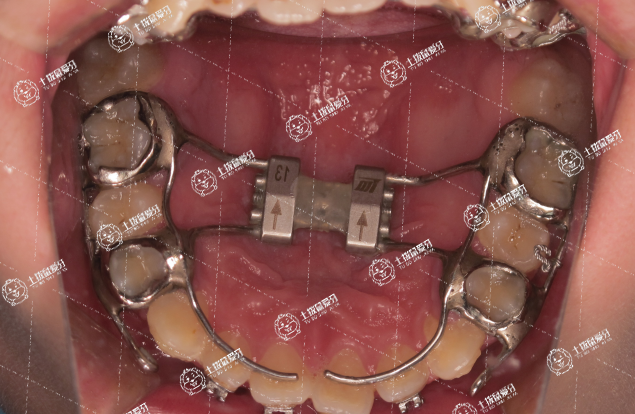

擴弓器又名牙弓擴大螺旋器,通俗的說就是一種讓牙弓變大的工具,它的作用是調(diào)節(jié)牙弓的大小,從而排齊牙齒,這樣可以避免矯正拔牙的情況,那到底做牙齒矯正選擇擴弓和拔牙哪個好?兩者各有優(yōu)缺點,建議大家要根據(jù)醫(yī)生推薦的方案而定,千萬不能盲目決定。

對于不想選擇拔牙矯正的顧客來說,擴弓器是一個比較好的矯正輔助工具,把擴弓器的兩端固定在后牙上,通過擴張的彈性裝置,即可改善牙弓狹窄、上頜牙弓過小等情況,佩戴方便,周期短。